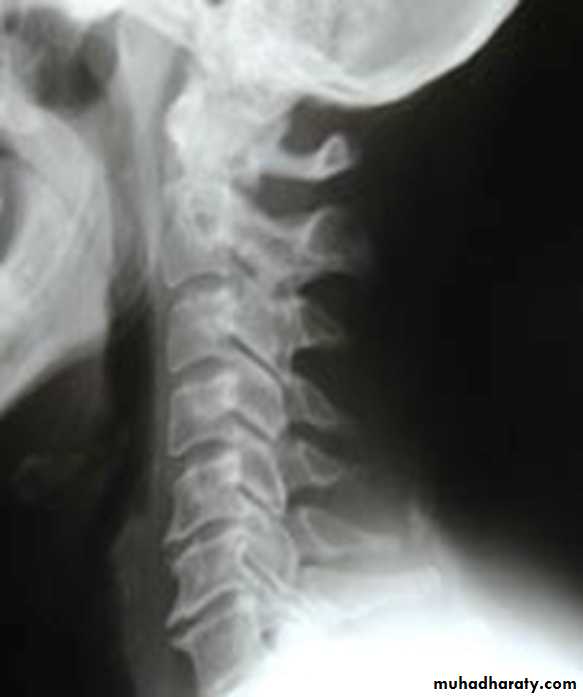

Cervical spondylosis

* Lower cervical and low lumbar spine are most comonly affected.* Osteophytes may encroach on neural foramina (best seen on oblique views).